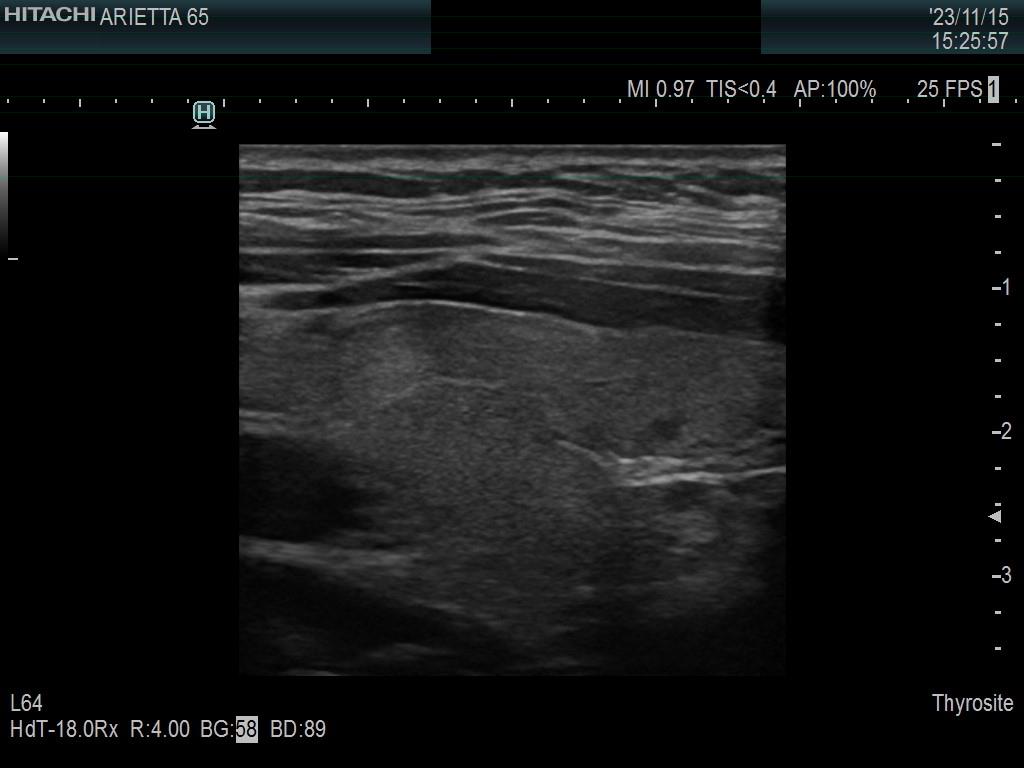

Ultrasonography. The thyroid was minimally hypoechoic. The echogenicity of the dorsal part of the left lobe where the nodule was previously described did not differ from other parts of the thyroid. There was a connective tissue running ventral to this part of the lobe and hypoechoic areas were found upper and dorsal to this. Neither halo nor perinodular blood flow was present.

The area in question did not correspond to a pathological nodule. It seemed to be circumscribed because of the presence of connective tissue and thyroid vessels.

A follicular tumor must have a capsule which ultrasound sign, either a complete halo and/or perinodular blood flow are present in more than 95% of cases. Both features were absent in this case.